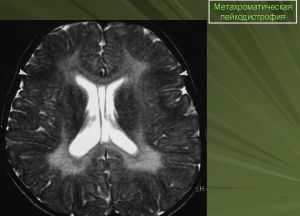

Метахроматическая лейкодистрофии Гринфилда—Шольца (син. поздняя инфантильная лейкодистрофия). Эту болезнь описали Шольц (W. Scholz) в 1925 г. и Гринфилд (Y. G. Greenfield) в 1933 г. Она наследуется по аутосомно-рецессивному типу. В основе патогенеза лежит врожденный дефицит активности энзима цереброзидсульфатазы (арилсульфатазы А), что приводит к прогрессирующей обширной демиелинизации и спонгиозной дистрофии ткани мозга и к отложению в виде гранул продуктов обмена — сульфатидов — в нервных клетках, нервных волокнах, глие разных отделов ц. н. с., гл. обр. подкорковых узлов, а также и в периферических нервах, сетчатке глаз, канальцах почек, лейкоцитах крови.

Метахроматическая лейкодистрофия в зависимости от манифестации имеет 4 варианта. Врожденный вариант дебютирует в первые 1-3 мес. жизни задержкой развития и судорожным синдромом; дети не достигают возраста 1 года. Позднедетский вариант метахроматической лейкодистрофии начинается в период от 1 до 3 лет с мышечной гипотонии и слабости, атаксии, задержки психического развития (ЗПР). Затем формируется спастическая тетраплегия, афазия, псевдобульбарный синдром. В редких случаях пациенты доживают до 10-летнего возраста. Ювенильный вариант манифестирует в 4-6 лет и длится в среднем 7 лет. Взрослый вариант дебютирует в третьей декаде жизни, иногда позднее, продолжительность жизни пациентов от начала клиники варьирует в пределах 10-20 лет.

Метахроматическая лейкодистрофия — одна из частых и изученных форм. Девочки и мальчики поражаются одинаково часто. При данной патологии отмечается дефицит лизосомного фермента арилсульфатазы. Этот дефект приводит к тому, что в белом веществе головного мозга, периферических нервов и органах (печень, легкие, почки, сердце) накапливаются специфические метаболиты сульфатиды, которые при гистохимическом исследовании дают специфическое метахроматическое окрашивание. Функция внутренних органов не страдает, а в мозговом веществе прогрессируют дегенеративные изменения. Метахроматическая лейкодистрофия по клинике делится на типы: врожденный, поздний инфантильный, ювенильный (ранний и поздний) и взрослый. Все типы протекают с ухудшением двигательной и психической функции, но эти нарушения возникают в разный возрастной период и степень прогрессирования тоже разная.